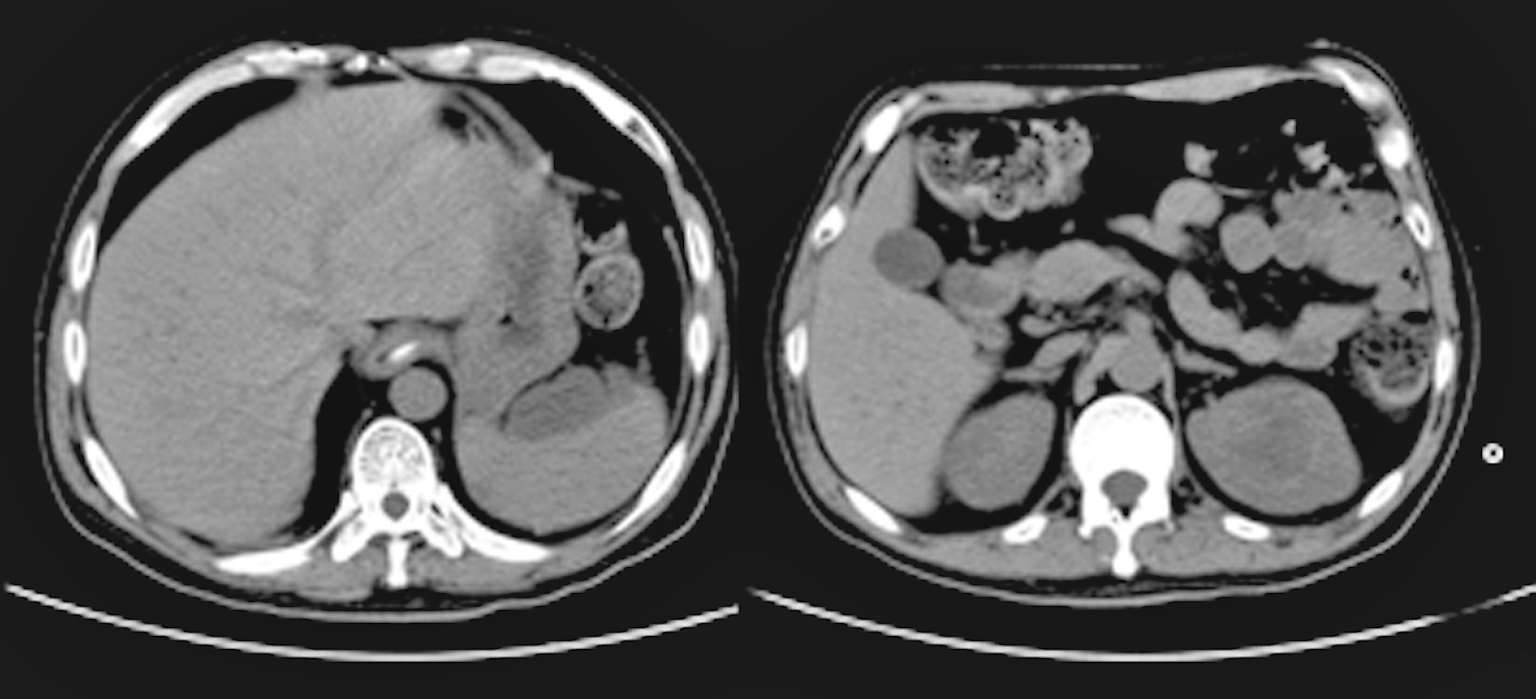

2018年7月12日晨家人发现患者倒地,当时呼之能应,精神萎靡,但四肢瘫软无力,胡言乱语,大小便失禁。至江苏省当地人民医院就诊,体温39.2℃,伴颈强直,脑膜刺激征阳性,肺部可闻及少许啰音。胸部CT(图2-1)示“右下肺见类圆形团块状稍高密度影,其内见气体影,右肺上叶近空洞样稍高密度影,周围见胸膜牵拉,胸膜不规则增厚。头颅CT示:脑内多发斑点状、小片状模糊密度影”。腹部CT(图2-2)示:肝脏、脾脏数枚小低密度影,肛周、脾周少许包裹性积液;左肾上极占位。给予布洛芬口服退热,但患者出现神志模糊,对答不切题,伴有可疑的癫痫发作,请神经内科会诊后考虑结核不能排除,遂转至南通市某医院呼吸科就诊。追问病史,患者起病前两周曾有上呼吸道感染病史,表现为少许咳嗽咳痰。

图2-1 2018年7月13日肺CT平扫:右下肺见类圆形团块状稍高密度影,其内见气体影,右肺上叶近空洞样稍高密度影,周围见胸膜牵拉,胸膜不规则增厚

图2-2 2018年7月13日腹部CT平扫:肝脏、脾脏数枚小低密度影,肛周、脾周少许包裹性积液;左肾上极占位